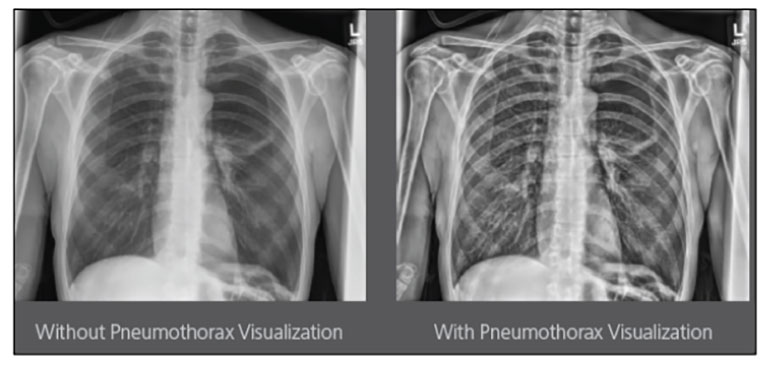

CARESTREAM Image Suite V4 MR11 has set a new standard for workflow efficiency, offering a robust set of features and functionalities to enhance clinical confidence in healthcare professionals. Using an auto-generated companion image from a single exposure, leverage a range of image processing options to increase diagnostic accuracy and enhance patient care.

Our Carestream Focus HD 35/43 Retrofit Detectors, powered by Image Suite Software, are an ideal solution to step up to full digital X-ray for customers who simply cannot compromise on image quality. It seamlessly integrates into existing setups, bringing the power of full digital X-ray with minimal disruption and maximum clarity, along with the following benefits: